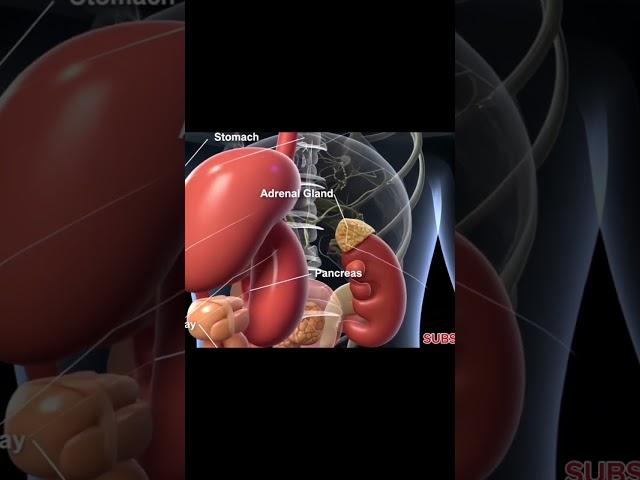

Exploring the 3D Anatomy of the Abdomen

Exploring the 3D Anatomy of the Abdomen